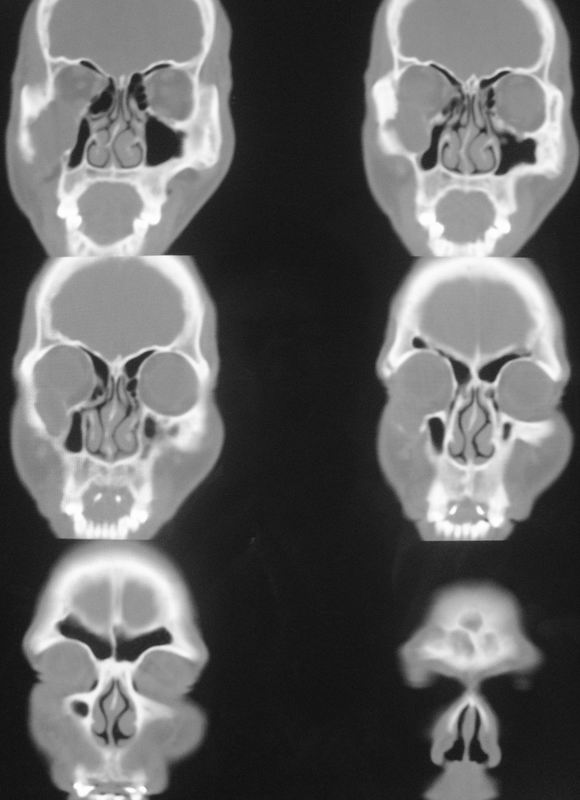

以下是引用zsl6918在2008-5-6 14:41:00的发言:[br]右侧颞下窝内囊性占位(增强未见强化),同侧上颌窦受压变形移位,提示慢性过程。右侧上颌骨局限性吸收破坏,提示良性病变。

以下是引用长城干红在2008-5-6 15:05:00的发言:[br]考虑:右侧颞下窝神经源性良性肿瘤。

以下是引用xuhuihong在2008-5-6 14:57:00的发言:[br]右侧颞下窝内囊性占位(增强未见强化),同侧上颌窦受压变形移位骨质吸收变薄,提示慢性过程。右侧上颌骨局限性吸收破坏,提示良性病变。考虑神经源性肿瘤可能,期待结果。